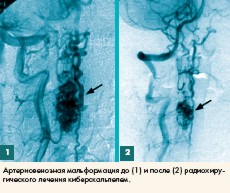

Киберскальпель (KiberKnife) для стереотаксической радиохирургии - сплав высочайшего уровня человеческого интеллекта и самых современных технологий кибернетики и медицинского приборостроения. С его разработкой и внедрением начался новый этап прецизионной органосохраняющей радиохирургии опухолевых и опухолеподобных образований. До появления киберскальпеля под стереотаксической радиохирургией понимали медицинские вмешательства по доставке высоких доз радиоактивного излучения в так называемые мишени (опухоли и опухолеподобные образования) мозга человека. Эти неинвазивные "оперативные вмешательства" - эффективная альтернатива в равной степени и хирургическим операциям, и системным методам лучевой терапии.

Киберскальпель же представляет собой "интеллектуальную" систему, которая обеспечивает многопозиционную прецизионную доставку радиоактивного излучения в мишень в любой части человеческого тела. Доставка осуществляется под управляемым изображением на основе компьютерного рентгеновского или магниторезонансного сканирования.

Во время проводимого радиохирургического лечения неизбежные изменения положения тела пациента контролируются камерами киберскальпеля. Используя эту информацию, робот осуществляет перефокусировку динейного ускорителя перед введением в мишень очередной дозы целительного пучка. Киберскальпель, получается, располагает собственной эффективной виртуальной стереотаксической системой и не нуждается в дополнительных механических приспособлениях. Именно поэтому его применение не ограничивается радиохирургией головного мозга.

Если в традиционных радиохирургических системах врач вынужден полагаться только на свой опыт и интуицию, то при использовании киберскальпеля он более всего опирается на результаты рассчитываемых киберскальпелем оптимальных моделей радиоактивного воздействия. Высокоманевренный робот на основании расчетов доставляет лечебное излучение исключительно в мишень. Точность киберскальпеля впечатляет - 1,1 мм! Она превышает точность считавшегося самым совершенным до него гамма-скальпеля - 1,7 мм.